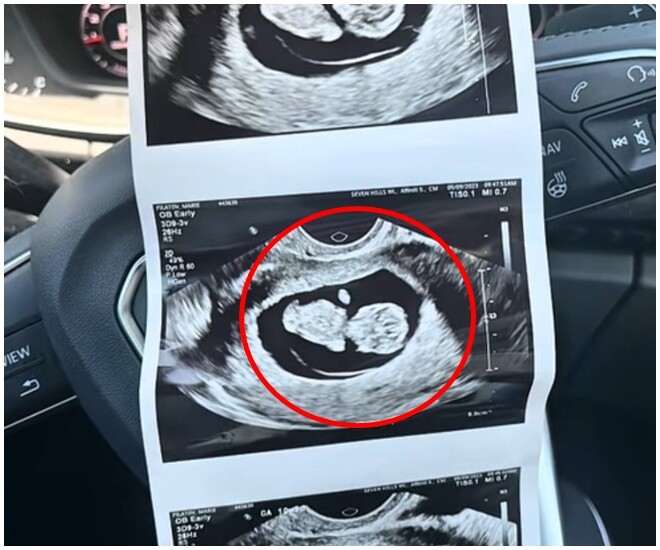

“I was ecstatic about becoming a mom for the first time. But that ultrasound changed everything. When the doctor finished, he gently said, ‘Everything looks good… except your baby is missing her left hand,’” Marie recalled.

The ultrasound revealed the baby was missing her left hand.